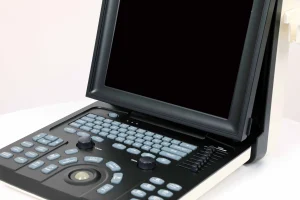

| Pantalla | LED de 12,1″ |

| Resolución | 1024 × 768 píxeles |

Alta definición de imagen: pantalla LED de 12,1″ con resolución de 1024×768.

Diseño robusto: materiales metálicos y plásticos que aseguran durabilidad y portabilidad.

Portabilidad profesional: su diseño robusto y compacto lo convierte en una herramienta ideal tanto para hospitales como para clínicas móviles o veterinarias de campo.